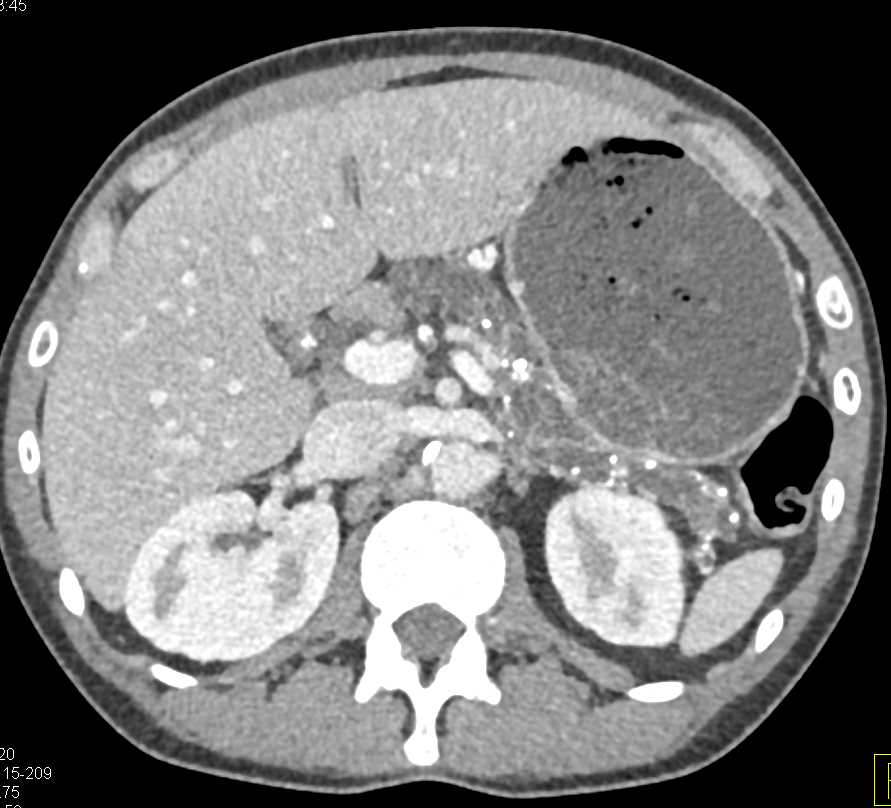

Vasculitis with Thickening Along the Superior Mesenteric Artery (SMA)